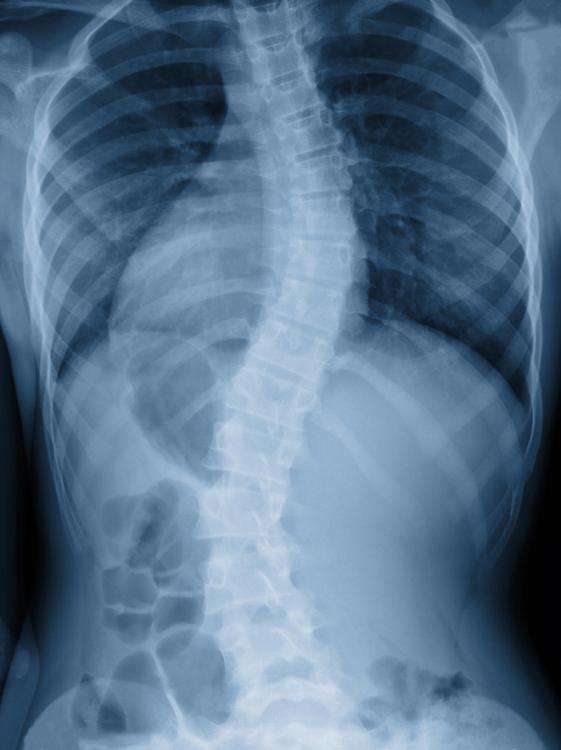

Una vez más apelamos a los corazones solidarios que se encienden cada vez que alguien lo necesita. Victoria tiene 10 años pero su vida cotidiana se le va haciendo cada vez más difícil ante un diagnóstico de escoliosis, que avanza y su columna va quedando afectada.

"Ella tiene obra social y le cubre el 80% y el 20% debo reunir yo. Yo tengo que pagar en la clínica 200 mil por día y estará 10 días. También hay que pedir los tornillos, en total es casi 6 millones que no sé de dónde sacar".